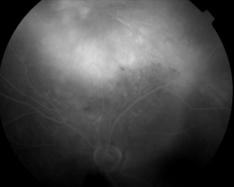

IM000030.jpg